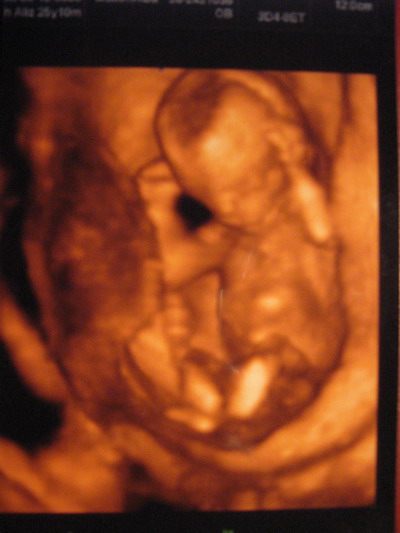

Csajok!Fantasztikus élmény volt!!!!

Eszike! Ha teheted, ne hagyd ki. Ne hagyja ki senki sem. Ott könnyeztem, hogy ez a csoda ott van bennem, és fantasztikus volt látni, ahogy megelevenedett bennem!Egy nagy plazmatévén volt kivetítve az egész vizsgálat.

Nos. Itt a sztárfotó!! :D :D :D

Fényképeznem kellett, remélem azért látható lesz minden.

A fejecskéjén az a sötét folt erről azt mondta a doki, hogy a fény, vagyis ahogy az UH így rávetítődik a fejére. Vagy valami ilyesmi..:shock: rövid az agyam.

-a fején az a sötét folt állítólag a kutacsa :) én is kérdeztem, hogy mi az a sötét lyuk? -hát a kutacsa a babának anyuka. - ez volt a válasz.